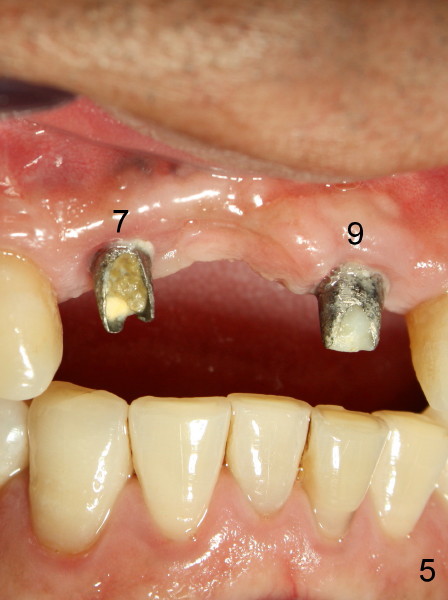

Fig.1 was taken when the new bridge was temporarily cemented (mirror view, Jan. 28, 2010). Arrowheads indicate enamel chip from the lingual cusps of the upper 2nd premolars. On Nov. 11, 2010, the bridge became loose again and was cemented permanently. Two months later (Jan. 27, 2011), porcelain chipped again as shown in Fig.2 and 3 (white arrowheads; black arrowhead points to wear facet of the tooth #6). The chipped bridge was removed.

This time PFM FPD was fabricated with lingual metal as shown in Fig.4. The bridge was temporarily cemented on Feb. 09, 2011. Night guard was fabricated later. Unfortunately the bridge came off 7 months later and was recemented temporarily. Permanent cementation was not attempted, because of potential porcelain chip or implant/abutment screw loosening due to bruxism. Yesterday, the patient reported that the bridge was loose again. Today, #7 build-up changed from loose, disintegrated Cavit to more solid composite (Fig. 5 to 6). The bridge was cemented temporarily to avoid porcelain chip related to permanent rigid cementation. Fig.7 shows occlusal equilibrium after cementation. The patient felt that there was no premature contact to the bridge. What should we do next? Can we add an implant at the site of #8. Can this alleviate bruxism-related problems (easy decementation, porcelain chip and possible loosening of screw between abutment and implant)? Thanks.